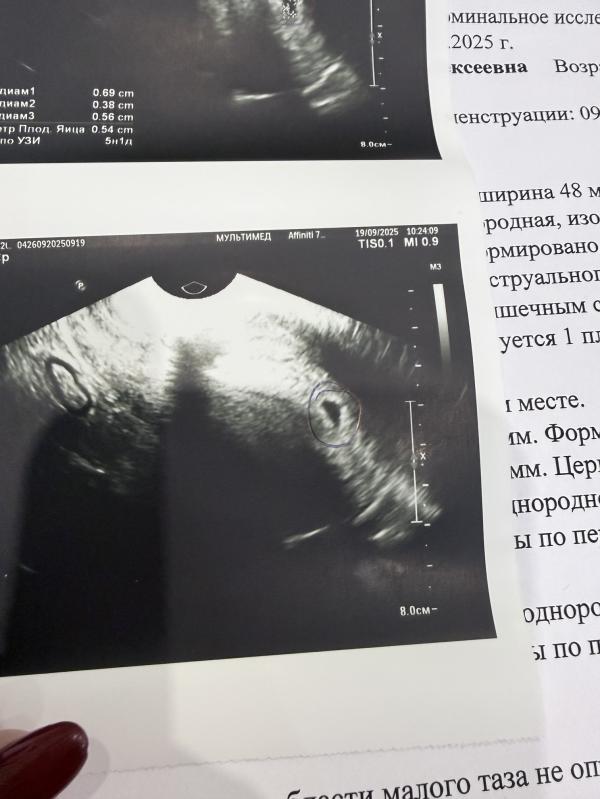

Первое УЗИ на 5 неделе беременности: эмоции и ожидания

Съездила на первое узи, не вытерпела🙈 срок поставили 5 недель 1 день, через недельку можно будет послушать сердечко и вставать на учет ☀️